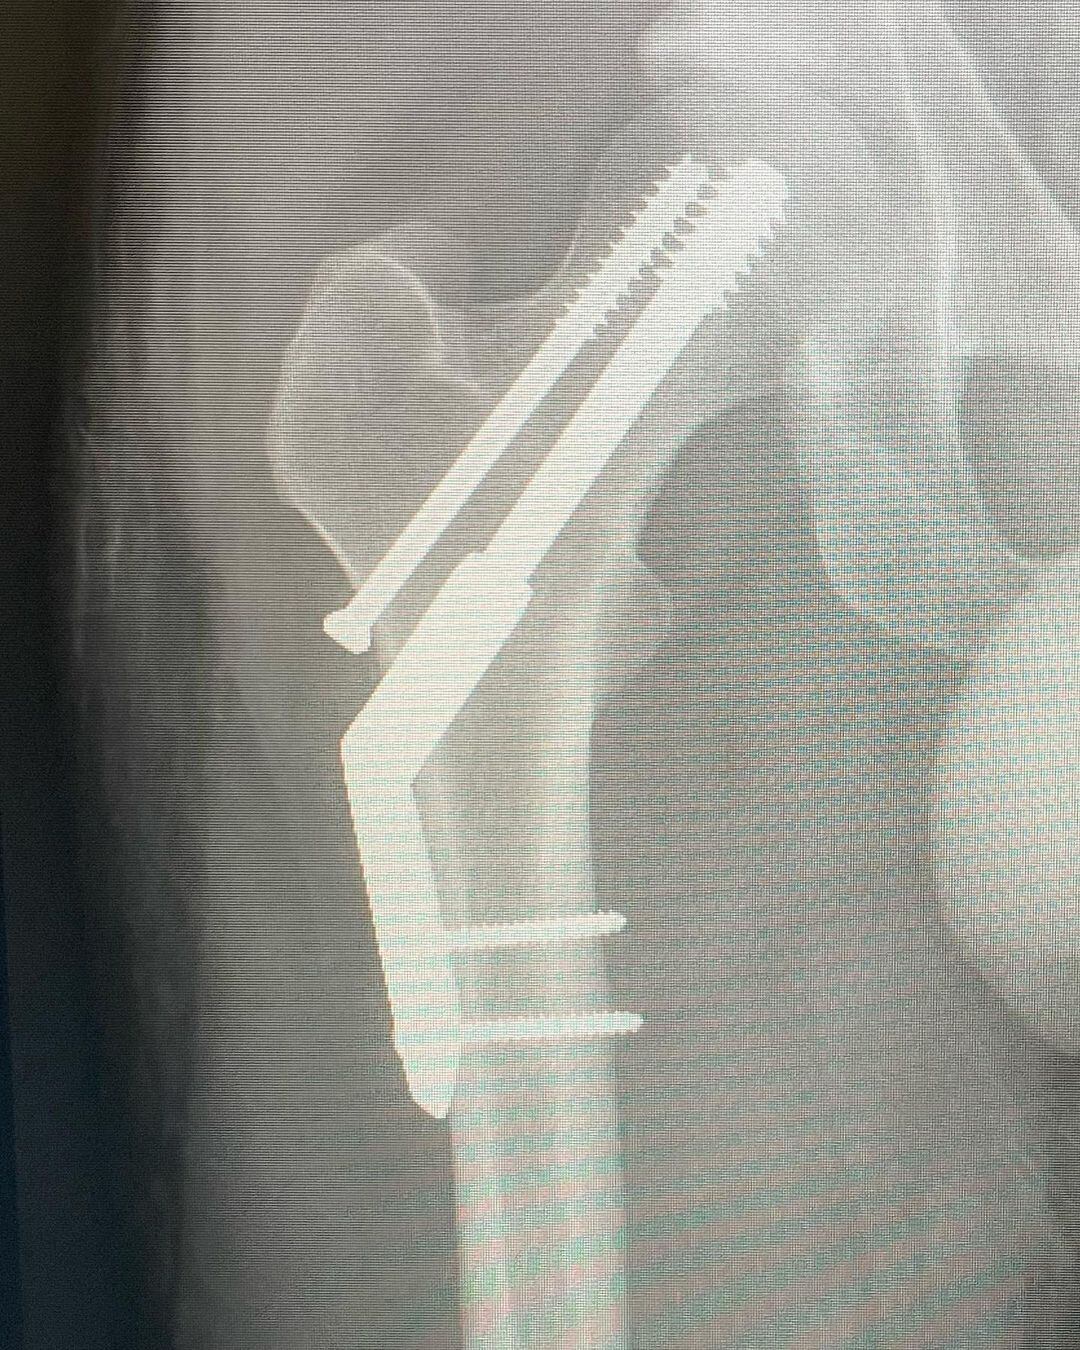

El cantante de la banda Tame Impala, Kevin Parker, reveló fotos de la fractura de su cadera a días de su presentación en el país.

Kevin Parker, el cantante de Tame Impala, se fracturó la cadera antes de su presentación en Lollapalooza Chile 2023.

El músico australiano, encargado de dar vida al proyecto psicodélico, preocupa a sus seguidores al informar en sus redes sociales que se fracturó la cadera corriendo una maratón.

“Me fracturé la cadera. Traté de correr una media maratón en lo que resultó ser una fractura por estrés existente. Ups. Llegué a menos de 1 km de la línea de meta. Así es la vida, supongo. Todos los espectáculos en México y Sudamérica van adelante como lo planeado, no voy a renunciar a ustedes chicos ❤️”, posteó el artista.